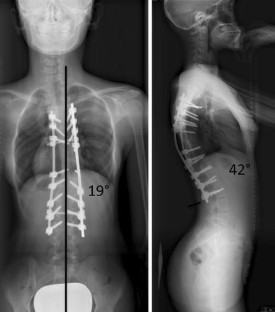

Fig. 4